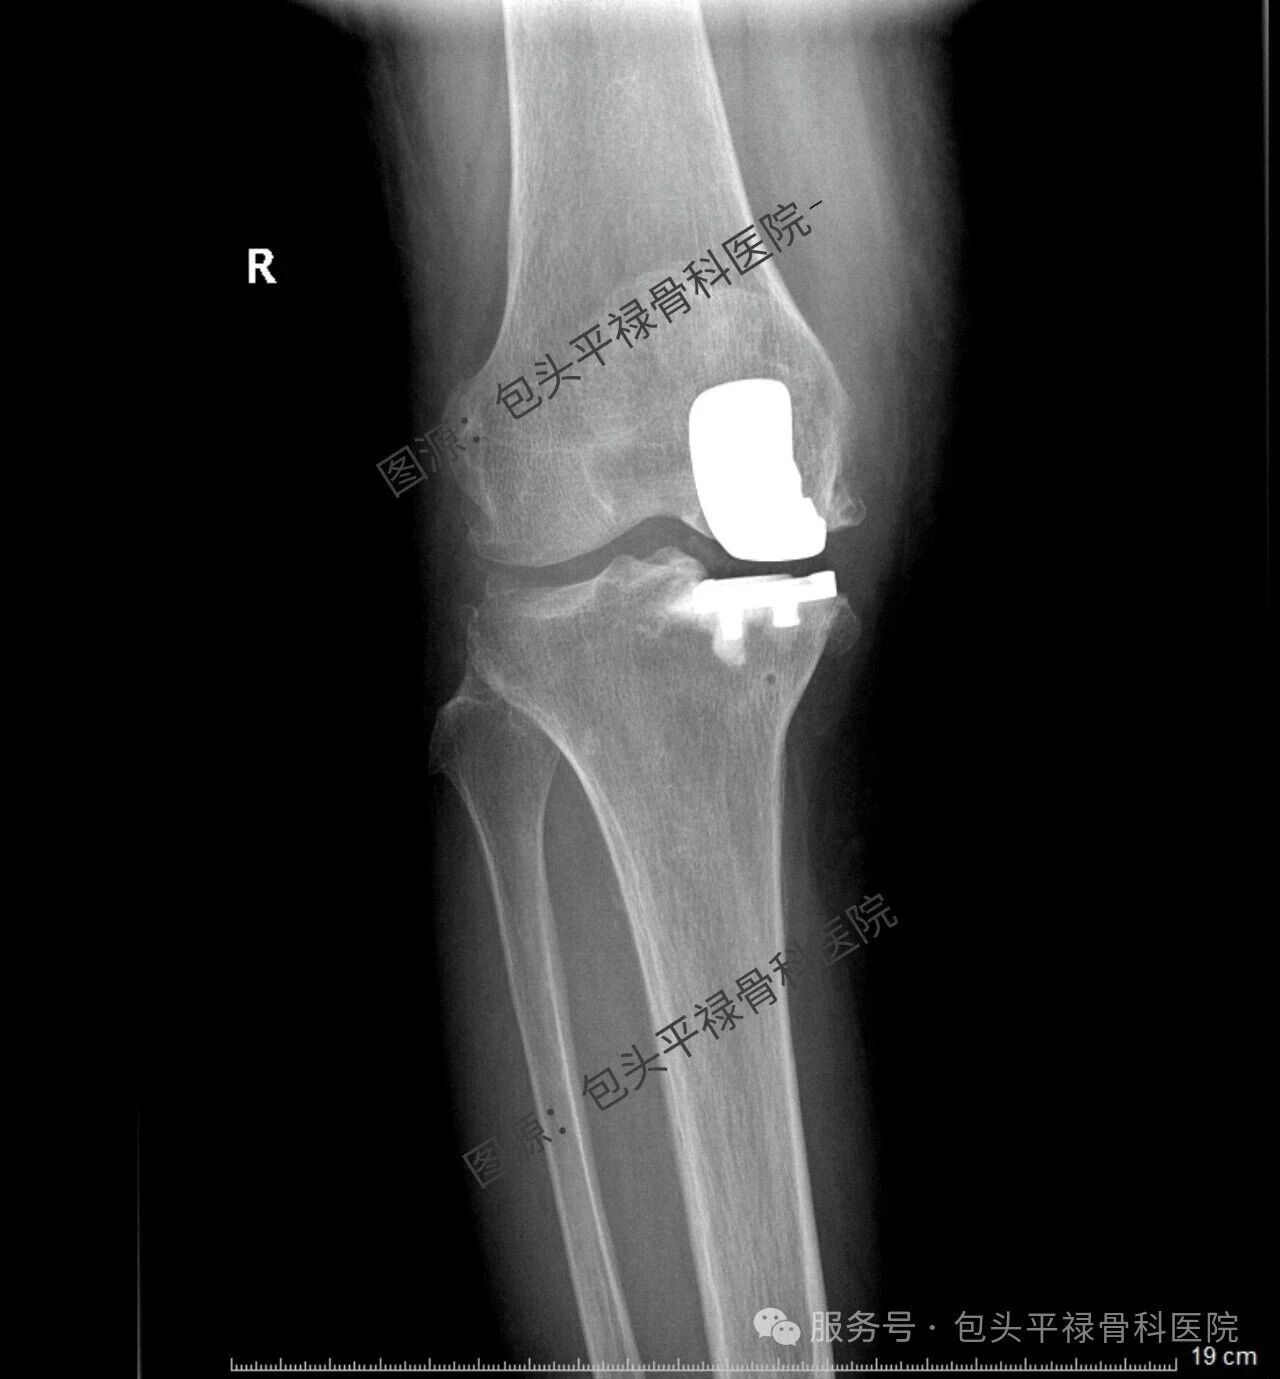

膝关节“局部维修”:带你了解膝关节单髁置换

其实,现代医疗技术日趋精准,如果患者的关节炎只局限于膝关节的一个部分(单侧间室),那么TA很可能适合一种更为精准、创伤更小的手术——膝关节单髁置换术。

单髁置换:精准的“局部翻新”

膝关节单髁置换术相当于“局部翻新”,就是只置换“坏掉房间”的磨损表面,仅将受损的软骨和部分骨质去除,替换为人工假体,而完好的软骨、交叉韧带及其他结构都得以最大程度的保留。